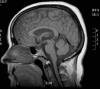

La exploración neurológica fue normal a excepción de una leve limitación de la abducción en el ojo derecho, por una posible afectación del VI par craneal derecho. La tomografía computerizada que se solicitó estuvo dentro de la normalidad y en la resonancia magnética (RM) se apreció el signo de la silla turca vacía, sin observarse ninguna lesión ocupante de espacio ni trombosis de senos venosos (fig. 3). En la punción lumbar la presión de apertura fue de 35 cm de H2O.

Fig. 3: Resonancia magnética nuclear en la que se observa el

signo de la silla turca vacía y el espacio correspondiente lleno de líquido.Fig.

2.